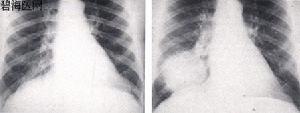

1、胸部X線檢查對肺動脈高壓的判斷有一定幫助,但無一徵象能準確地反映出肺動脈高壓的程度。常用於提示肺動脈高壓的X線徵象有:

①右下肺動脈橫徑增寬,國人正常值小於15mm;

②肺門寬度與1/2胸廓橫徑比增加,即從前正中線至肺動脈段緣間的距離與1/2胸廓橫徑之比,正常值為(28.1±4.5)%;

③肺門胸廓指數增加,即從前正中線水平至左、右肺動脈主要分支間距離之和與整個胸廓橫徑之比,正常值為(34±4)%;

④肺動脈段突出,正常值小於3mm;

⑤肺門動脈擴張與外圍紋理纖細形成鮮明的對比或呈“殘根狀”;

⑥右心房、室擴大;

⑦心胸比率增加,正常小於0.5。需指出,輕、中度原發性肺動脈高壓的胸部X

線可無異常所見,重症患者改變明顯,診斷的敏感性較高。